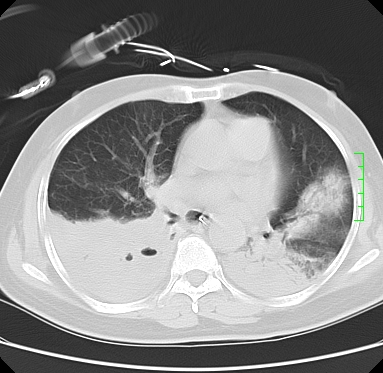

icu病人,几天都没明确诊断。m,76y,咳嗽、咳痰1周,伴气促,右胸痛入院,pe:t38.3c p135 r25 bp135/85。双肺可闻及大量湿罗音,心、腹未见明显异常。诊断:1心衰?2肺部感染?3冠心病?

11号ct

双肺感染性病变,下叶膨胀不全,胸水,左室大。

1)两肺感染性病变(右肺下叶肺脓肿可能)。2)双侧胸腔积液,以右侧为甚。

混合型肺水肿合并感染,肺膨胀不全,胸膜肥厚粘连包裹,同时肺内有陈旧性病灶。注意复查

ards,肺感染性病变,右下叶实变,双侧胸腔积液,右侧为著,叶间胸膜积液,右上肺陈旧性tb纤维灶,左室大。

考虑双肺感染、右肺下叶肺脓肿伴双侧胸腔积液,肺水肿。

考虑:双肺感染、右肺下叶肺脓肿,双侧胸腔积液,肺水肿.请结合临床.